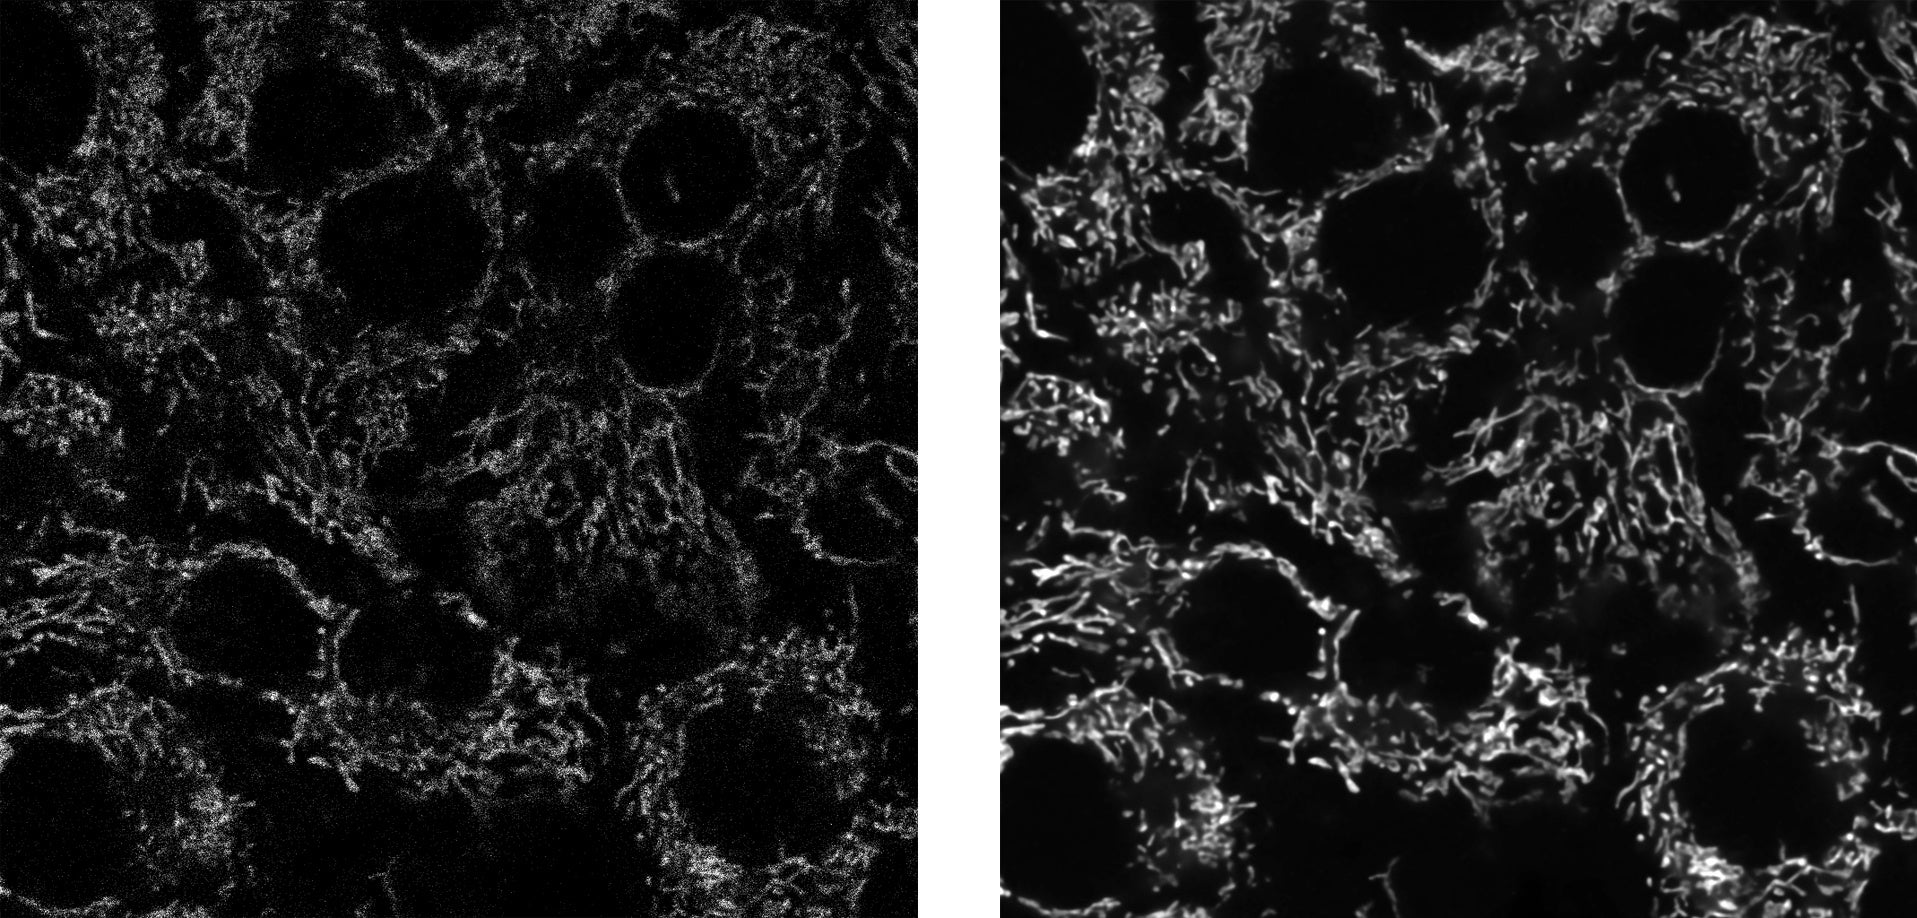

左:「TruAI」を使用せずに撮影した画像、右:「TruAI」によるノイズ低減処理後の画像

独自開発の画像解析技術「TruAI(トゥルーエーアイ)」を本製品向けに改良し、ノイズ低減機能を追加したことにより、高品質な画像取得が可能となりました。組織内の血液の動きや細胞間のシグナルの伝播などを高速かつ高精細に捉えることで、より正確な観察に寄与します。